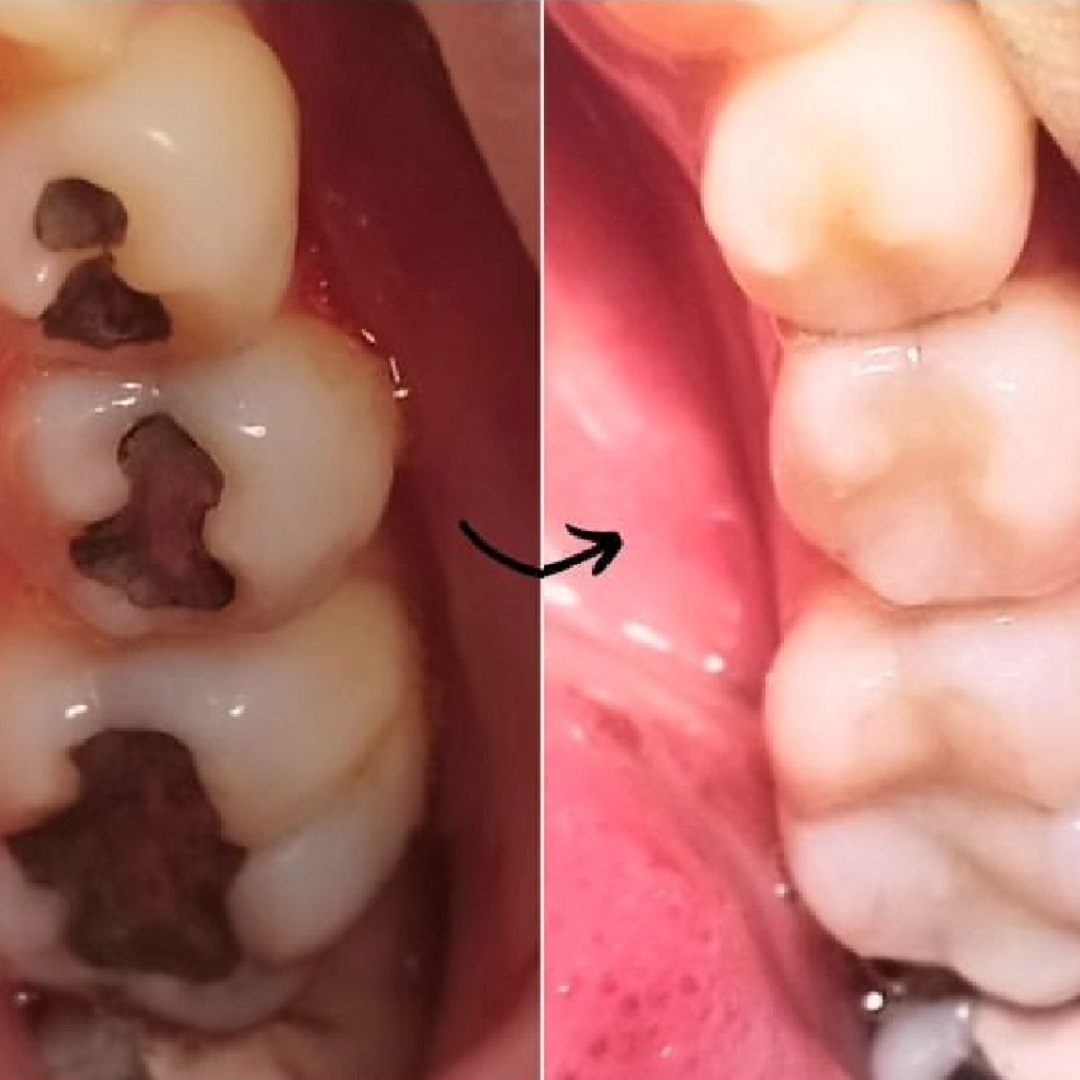

Restaurações